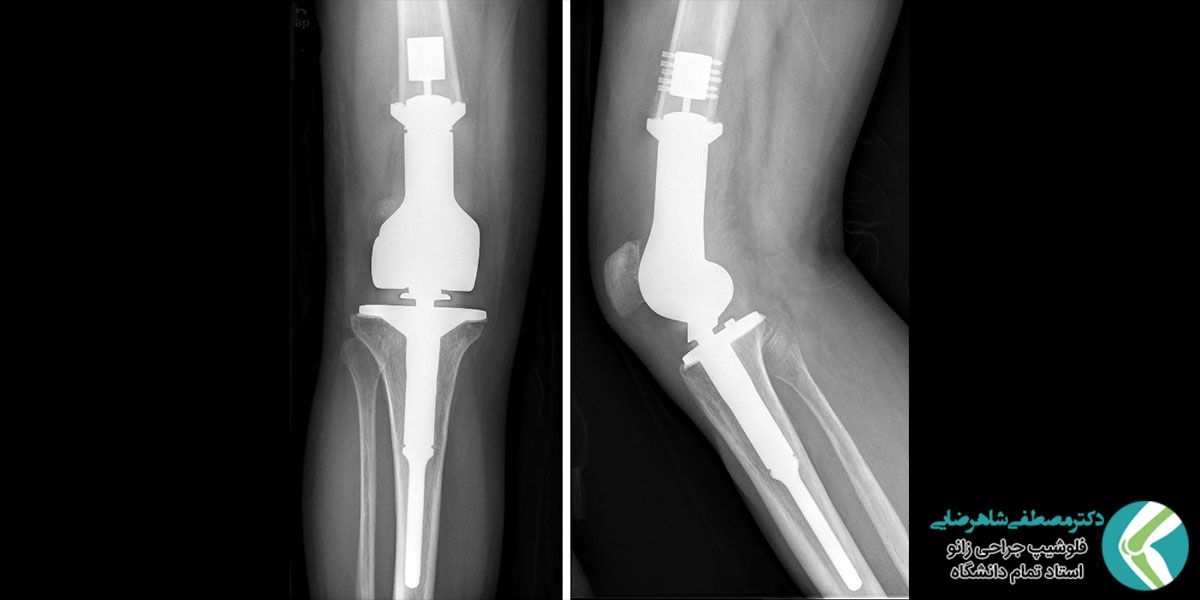

تعویض مفصل زانو یا آرتروپلاستی

بر اساس شدت آسیب وارده مشکلات مربوط به مفصل زانو به روش های مختلف برطرف می شود. متخصص ارتوپد در گام اول برای بهبود شرایط بیمار، روش های غیر جراحی را مدنظر قرار می دهد؛ به عنوان مثال می توان به دارودرمانی، تزریق مستقیم به زانو، تمرینات فیزیوتراپی، توانبخشی، کاهش وزن و تغذیه مناسب اشاره کرد. تمرینات فیزیوتراپی خود شامل حرکات ورزشی مخصوص، لیزر درمانی، درمان دستی، ماساژ، یخ درمانی و بسیاری موارد دیگر است. در صورت کارساز نبودن این روش ها به ناچار عمل جراحی ضرورت می یابد. گاهی میزان آسیب به حدی است که متخصص ارتوپد تصمیم به تعویض مفصل با پروتز یا مفصل مصنوعی می گیرد. عمل جراحی تعویض مفصل زانو در اصطلاح پزشکی آرتروپلاستی (Arthroplasty) نام دارد.

آرتروپلاستی به دو شیوه کامل و جزئی انجام می شود. در عمل جراحی کامل، جایگزینی هر سه قسمت پروتز از قبیل پاتلار (کشکک)، تیبیال (درشت نی) و فمورال (ران) در زانوی بیمار انجام می شود؛ اما در عمل جراحی جزئی تنها جایگزینی بخش آسیب دیده در دستور کار قرار می گیرد. ناگفته نماند که در بسیاری از بیماران تحت جراحی جزئی معمول ساییدگی در بخش های دیگر رخ داده و بعد از مدتی تعویض آنها نیز ضرورت می یابد. عمل تعویض مفصل زانو در تهران یا سایر شهرها به دو شیوه باز و بسته قابل انجام است. روش باز به یک برش ۸ الی ۱۲ اینچی در جلوی زانو نیاز دارد؛ اما در روش بسته طول برش ها به حدود ۳ الی ۵ اینچ کاهش می یابد. درنتیجه عوارضی چون درد، خونریزی و حتی دوره نقاهت کم تر می شود.

بخش های مختلف پروتز زانو به دو روش به استخوان های پیرامون مفصل زانو محکم می شوند. در اکثر موارد محکم کردن پروتز به استخوان توسط سیمان (نوعی چسب مخصوص) صورت می گیرد؛ اما گاهی اوقات متخصص ارتوپد از تثبیت بیولوژیکی استفاده می کند. در این روش صفحه متخلخل بین پروتز و استخوان قرار گرفته و به مرور زمان استخوان داخل حفرات آن رشد می کند. در صورت استفاده از ترکیب سیمان و تثبیت بیولوژیک در عمل جراحی تعویض مفصل، تجهیزات مورد استفاده پروتز هیبریدی نامیده می شوند.